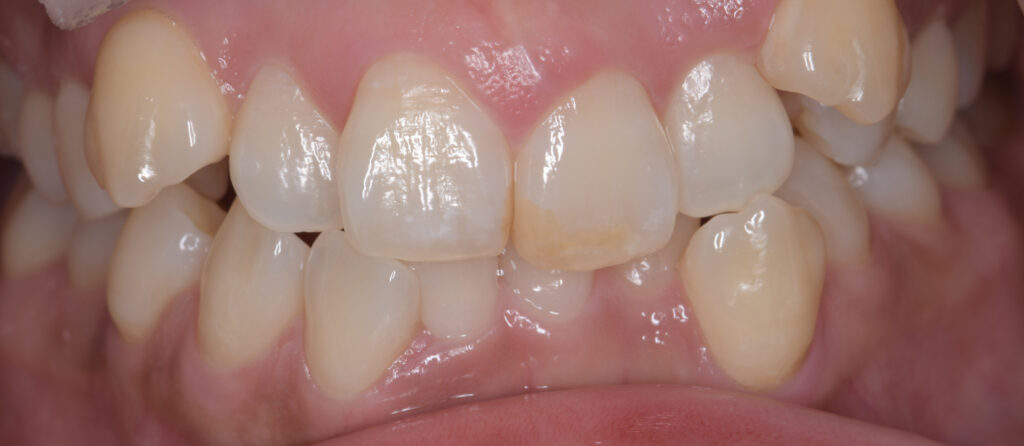

「歯の表面にある**茶色い点(ブラウンスポット)と、前歯に広がる白く濁った模様(ホワイトスポット・白濁)**が気になって…」

このようなお悩みで、墨田区・江東区・中央区エリアから…